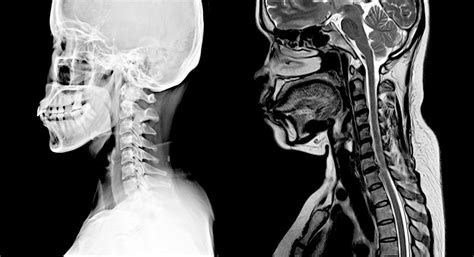

• X-rays: These use radiation to produce images of the bones in the cervical spine. They are useful for detecting fractures or other bone abnormalities but do not provide detailed images of soft tissues.

• normal cervical xray

• normal cervical mri sagittal view